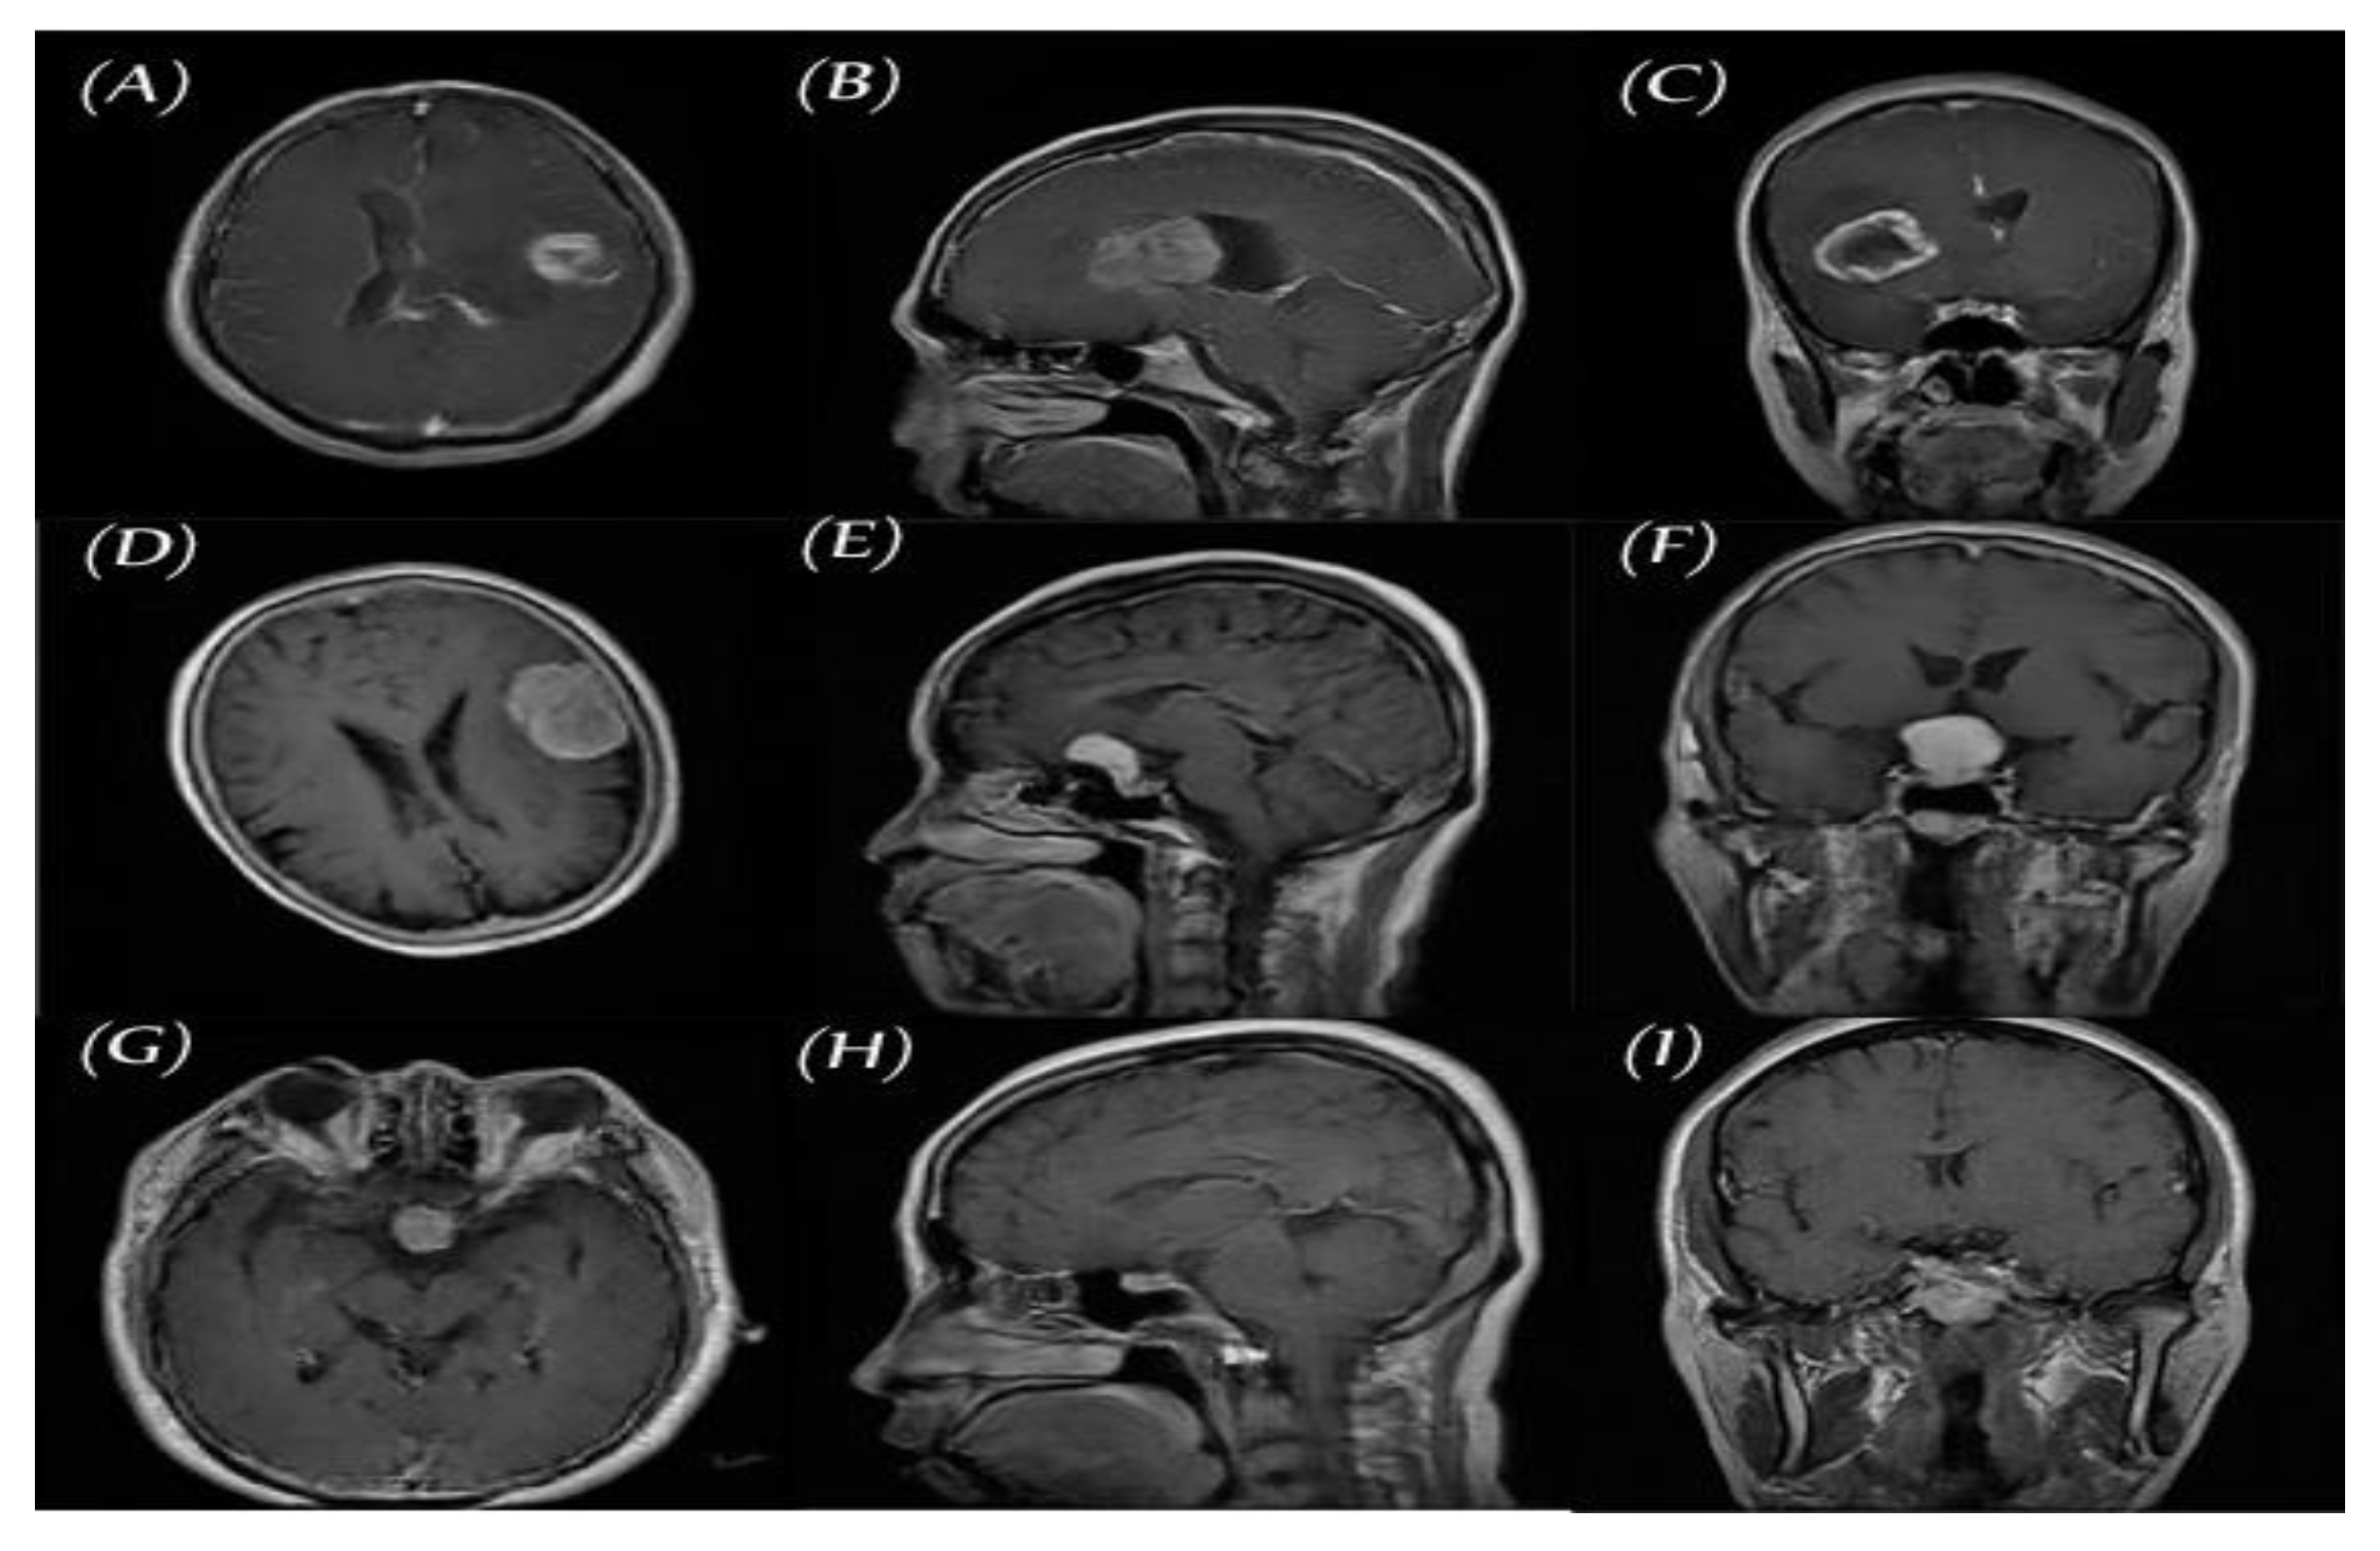

2.1. Data set for the Study

2.2.1. Classic Data Augmentation

- Rotation: Rotation of image without cropping because a cropped image may not contain the whole tumor. Images were rotated at 90, 180, and 270 degrees;

- Mirroring: Images are right/left mirrored;

- Flipping: Images are up–down flipped.